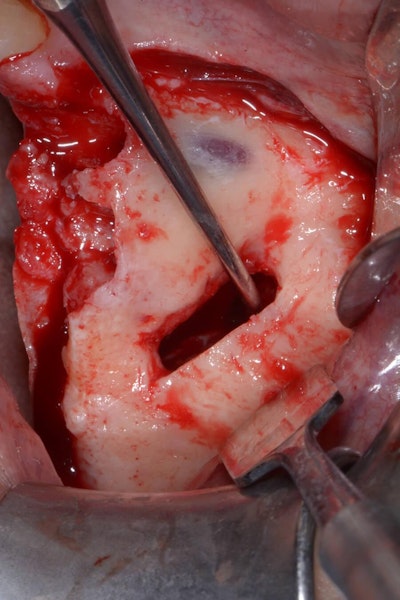

An incision is made along the crest with vertical releasing incisions to obtain access to the lateral and anterior walls of the sinus. The extension of the flap is smaller than a traditional sinus elevation. Once a full-thickness flap is elevated, a small antrostomy is made parallel to the anterior sinus wall starting 3 mm distal to it and then extending anteriorly to reach the anterior sinus wall. The antrostomy is usually 4 to 6 mm mesiodistally and 7 to 8 mm apicocoronally. This simplified antrostomy design is preferred because extension of the antrostomy to the anterior wall renders the membrane elevation procedure simpler and safer by providing direct visual access to the narrow anterior portion of the sinus. This results in a reduced membrane perforation rate (Fig 2a-b).

The antrostomy is parallel to the anterior sinus wall. The membrane has been distally displaced and the nasal mucosa is gently elevated to allow implant site preparation.

Distal displacement of the sinus membrane allows for the placement of an implant with a distal tilt of 30 degrees (Fig. 3). The direction of the first implant drill can be observed through the antrostomy. The preparation of the implant site extends apically through the anterior sinus wall into the cortical layer of the often adjoining lateral nasal wall. After verification of the implant axis using direction indicators, the drilling sequence is finalized and a bone substitute is inserted (on average, 1 mL of graft material is needed). The implant is then inserted through the residual crestal bone into the grafted sinus where the membrane has been previously displaced distally. It engages apically at the M point, the confluence of three cortical walls. In some cases, it may be possible to obtain satisfactory implant stability without engaging the lateral nasal wall cortex. This approach further simplifies the surgical procedure.

The implant drill is used at a 30 degree angle.